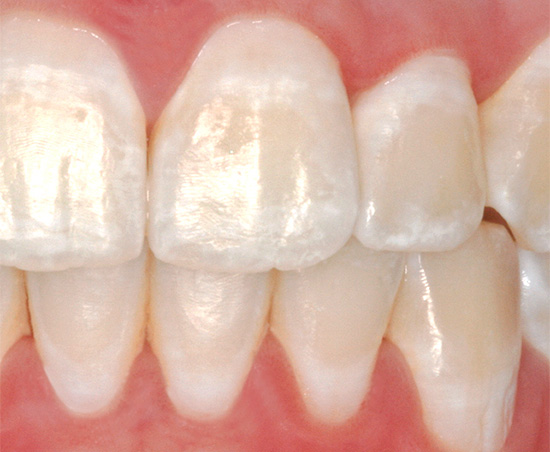

É importante entender que, em casa, é possível tratar a cárie apenas no primeiro estágio inicial, quando uma lesão dentária parece um ponto brilhante. Nesta fase, com a ajuda de medidas e meios especiais, é completamente possível interromper a destruição adicional do esmalte e, além disso, garantir a introdução de componentes minerais nele para restaurar o estado saudável inicial.

- A cárie em si se parece com um ponto branco liso.

Uma mancha branca no dente é formada durante a desmineralização de uma fina camada de esmalte na superfície. Seus principais componentes - hidroxiapatites e fluorapatitos - são dissolvidos por ácidos da cavidade oral e lavados. Se você reduzir a quantidade desses ácidos e aplicar regularmente nos dentes as substâncias das quais se formam os apatitos secundários, em particular compostos de flúor e cálcio, essa camada de esmalte poderá ser restaurada.